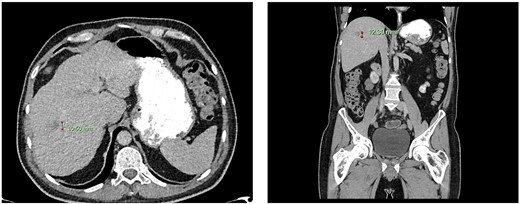

Computed tomography dated 25 September 2012 of the abdomen and pelvis measuring 18.65 mm (anterior–posterior) lesion at liver segment 5/6 in axial (left) and coronal (right) view.

Subsequent surveillance imaging including magnetic resonance imaging and CT scans demonstrated gradual reduction and eventual complete resolution of the liver metastases (refer to Figs 1–4). Furthermore, routine colonoscopy and a positron emission tomography (PET) scan revealed no evidence of locoregional cancer recurrence nor distant metastatic disease present; essentially rendering the patient cured from an initial diagnosis of metastatic rectal cancer. It has been at least a decade since his initial diagnosis and the patient remains in remission.